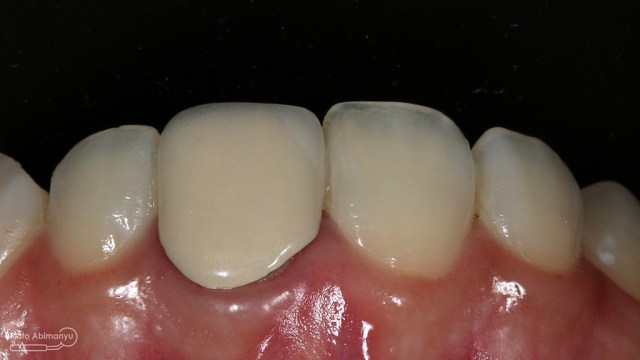

Oo iya tidak lupa juga dilakukan foto ronsen setelah pemasangan crown…

Foto radiografis akhir

Dari foto ronsen terlihat gambaran yang “indah” dari mulai pengisian saluran akar yang rapat dan padat serta gambaran sementasi mahkota yang terlihat homogen….